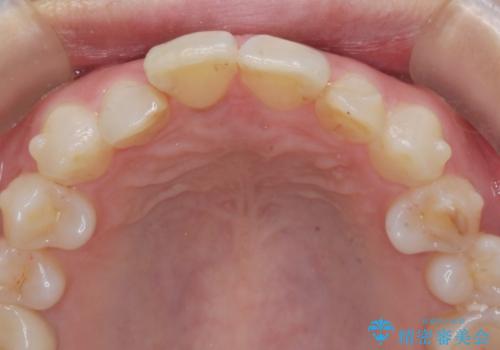

インビザラインで行う前歯のみの部分矯正

- 長年気になっていた前歯の歯並びを改善したいと、矯正治療を希望され思い切って来院されました。

費用と期間を相談し、「気になっているのは前歯だけ。」とのことでしたので前歯のがたつきのみをインビザラインで改善する矯正治療の計画を立てます。

しっかりとマウスピースの装用時間を守っていただき、非常にスムーズに治療を終了することができました。